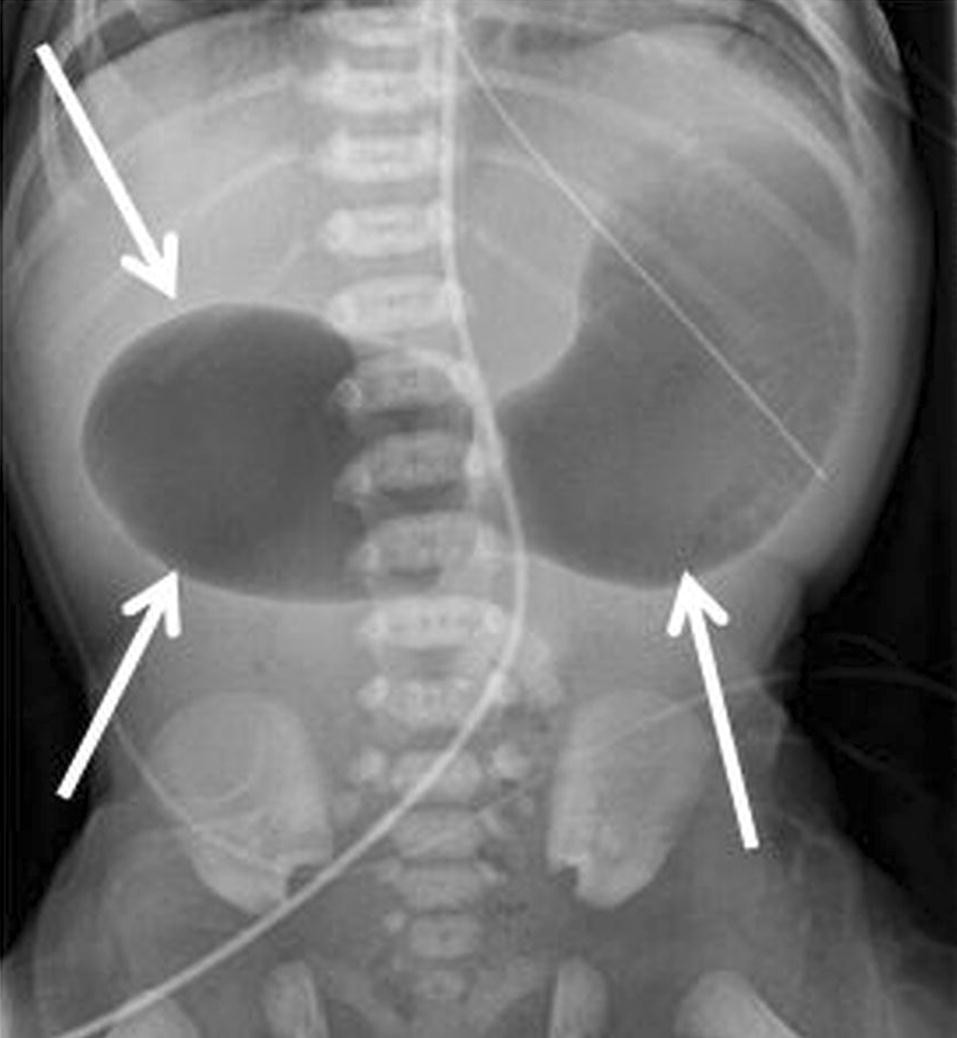

Medical News Radiology Mcqs For Usmle Aipgee And Plab Double Bubble Sign Causes Include A Congenital Obstruction Duodenal Web Duodenal Atresia Duodenal Stenosis Annular Pancreas B

シングルバブル、ダブルバブル、トリプルバブルサインの違い なになにバブルサインとは、消化管が閉鎖される疾患のレントゲン所見のこと。 シングルバブルサイン ダブルバブルサイン トリプルバブルサイン 画像 出典 出典:105D41 出典スクリーン ダブルバブル クリア honda vtr1000f '97 〜 '05 カラー:クリア タイプ:ダブルバブル ご注意 写真は実際の製品と異なる場合がございます。 16年3月22日からの新価格です。Double(ダブル)は、日本の女性 歌手、ソングライター、takakoによるソロ・プロジェクト。 姉妹デュオとして1998年にデビューしたが、1999年に姉のsachikoが急逝したため、以降は現在の形態となった。 06年からはdj lilly aka double(ディージェイ・リリー・エーケーエー・ダブル)名義

bubble バブル の値段はいくら? 今回はTWICEの画面で紹介するけど bubble バブル のアプリから値段を確認できるよ。 ここで注意したいのが、bubbleの登録はNiziUメンバー1人の値段ね。でも複数メンバー登録すると割引もあるよ。ダブルバブルサイン 上部消化管閉塞 十二指腸閉塞 ダブルマドックス杆検査 上部消化管閉塞 先天性消化管異常 メルクマニュアル18版 日本語版 特徴的徴候は,唾液過多,哺乳を試みた後の咳嗽とチアノーゼ,嚥下性肺炎である。 食道 遠 ★リンク